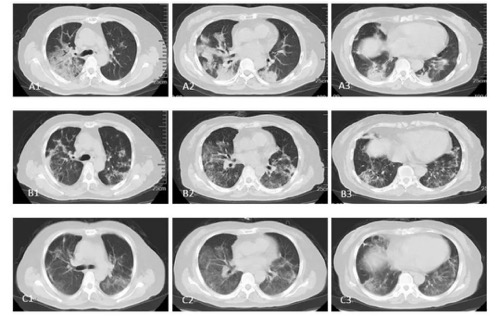

通過(guò)對(duì)比hUCMSCs治療前后的 胸部CT影像,可以看出患者的COVID-19病情得到了極大的改善。

圖中:A1-A3 1月29日;B1-B3 2月16日;C1-C3 2月21日